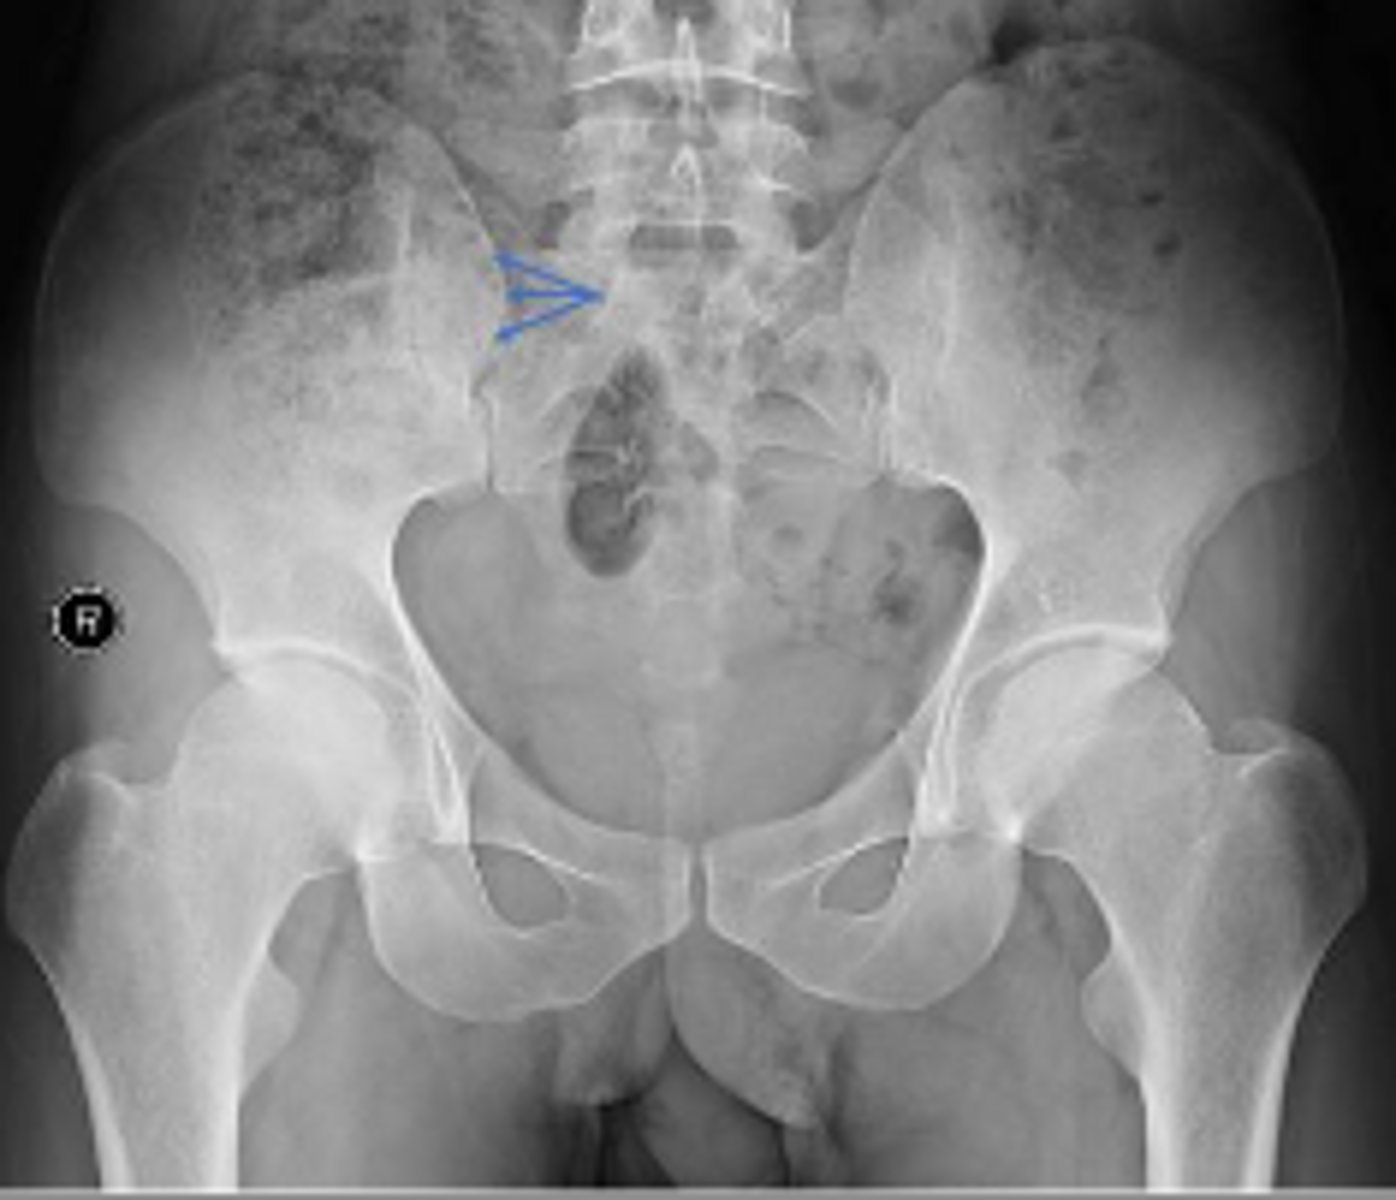

Posterior hip dislocation

What is most significant radiographic finding?

AP pelvis or bilateral hips

Name the radiographic view

What are the arrows pointing to?

Phleboliths